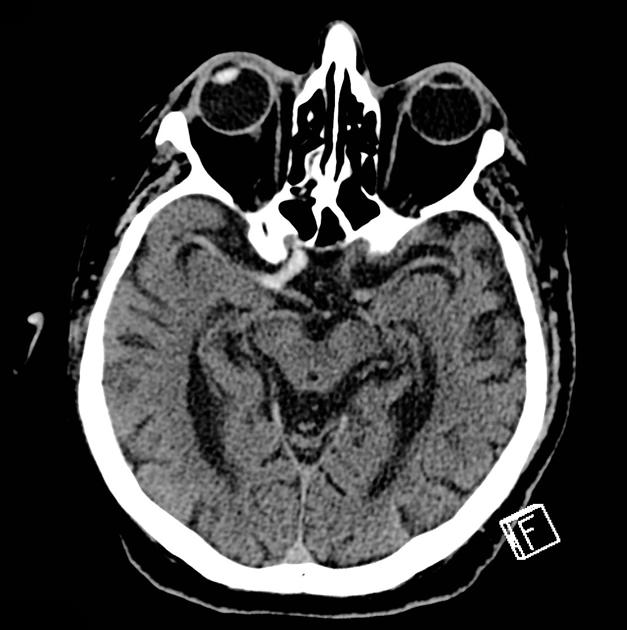

局部脑沟变浅与灰白质分界模糊

在脑梗死超急性期,患侧常出现脑肿胀,进而致使脑沟变浅。需要注意的是,不同年龄段患者的脑沟深浅存在差异,因此在判别时,对比两侧的对称性更具重要意义。阅片时,有个小技巧,适当调窄窗位和窗宽,能提高组织密度对比度,有助于更清晰地观察灰白质分界。